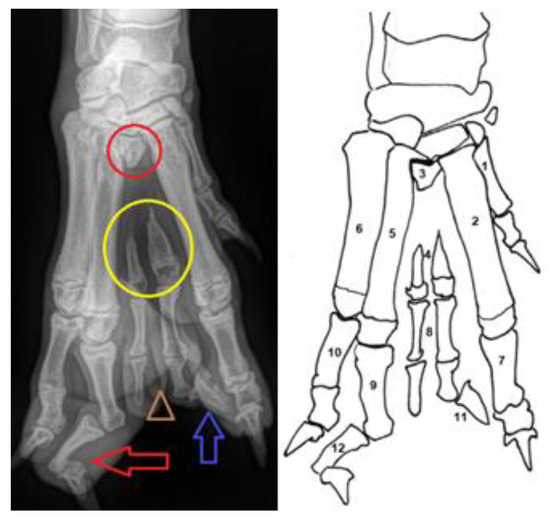

Figure 1.

Pre-operative Radiographs (left) and line drawing (right) of the abnormal paw. (1) first metacarpal bone; (2) second metacarpal bone; (3) rudimental proximal part of the third metacarpal bone (the red circle); (4) hypoplasia of the third metacarpal bone (yellow circle); (5) fourth metacarpal bone; (6) fifth metacarpal bone; (7) proximal phalanx of the second digit; (8) double confirmation of the proximal and medial phalanx of the third digit (marked with the brown triangle); (9) proximal phalanx of the fourth digit; (10) proximal phalanx of the fifth digit; (11) note that only a single claw was developed at the third digit (blue arrow); (12) medial phalanx of the fourth digit with severe valgus deformity and distal phalanx of the fourth digit with varus deformity (red arrow).

Dorso-palmar and medio-lateral radiographs of the right manus were obtained. The third digit showed a double conformation with only one claw. The third metacarpal showed an absent diaphysis with a proximal metaphysis, and two distal parts of the metaphysis and doubled phalanx were present. In addition, a severe valgus deformity of the second phalanx of the fourth digit with a varus deformity of the distal phalanx was observed in the presented case (Figure 2A).

There were no abnormalities of the carpus, antebrachium or elbow joint. The paw abnormalities seen in Figure 1, Figure 2A and Figure 3A supported the diagnosis of ectrodactyly and polydactyly of the third metacarpals. A physical examination of the dog revealed no other abnormalities or additional congenital anomalies.